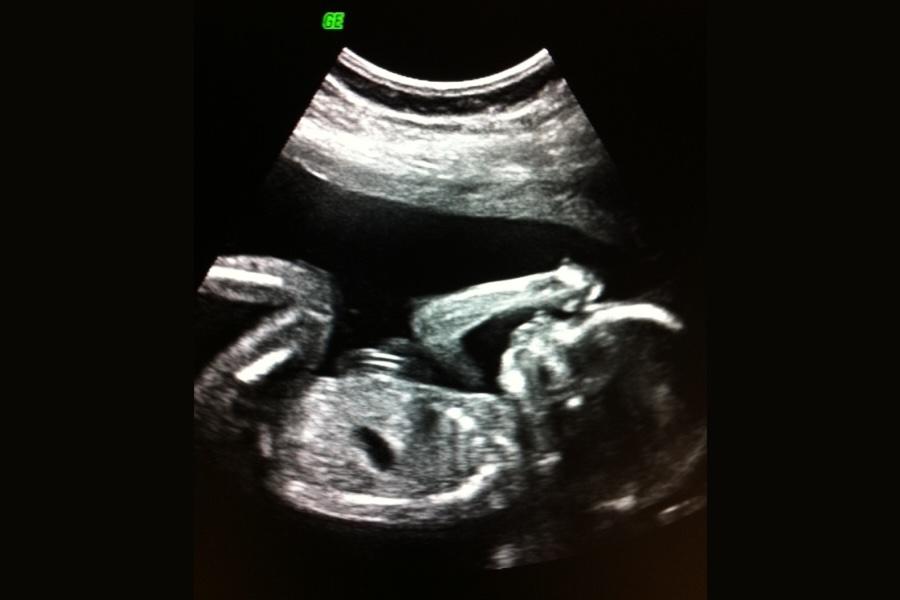

USG pozwala lekarzom monitorować rozwój dziecka, sprawdzać ruchy, tętno i ogólną anatomię. Jednym z najważniejszych badań jest badanie połówkowe około 18.-22. tygodnia ciąży, kiedy dokładnie analizowane są organy i kończyny dziecka. To również moment, w którym rodzice często mogą poznać płeć dziecka, ale przede wszystkim jest to kluczowy moment do wykrycia ewentualnych nieprawidłowości strukturalnych.